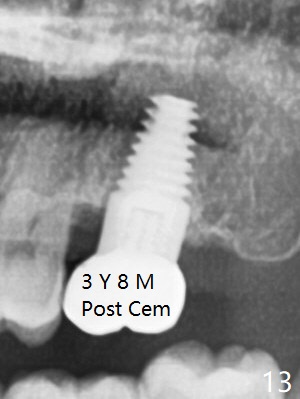

There is no bone loss 17 months post cementation (Fig.12). The patient reports that he has to keep cleaning well to prevent discomfort locally. Clinically, the gingiva is healthy around the implant crown. No bone loss is around the implant 3 years 8 months post cementation (Fig.13), but the natural teeth are not so fortunate (Fig.14).